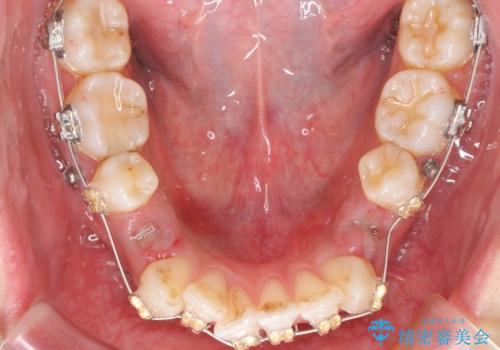

ガタつきと口元の改善 抜歯を伴うワイヤー矯正

- 唇の閉じづらさと、前歯のがたつきの改善を希望され来院されました。

抜歯を行わなくてもなんとか並べられる歯並びですが、唇の閉じづらさをしっかりと改善するため抜歯を伴うマルチブラケット矯正を行うこととしました。

前歯をしっかりと後方に引いたことで、唇は閉じやすくなり、仕上がりに満足いただくことができました。